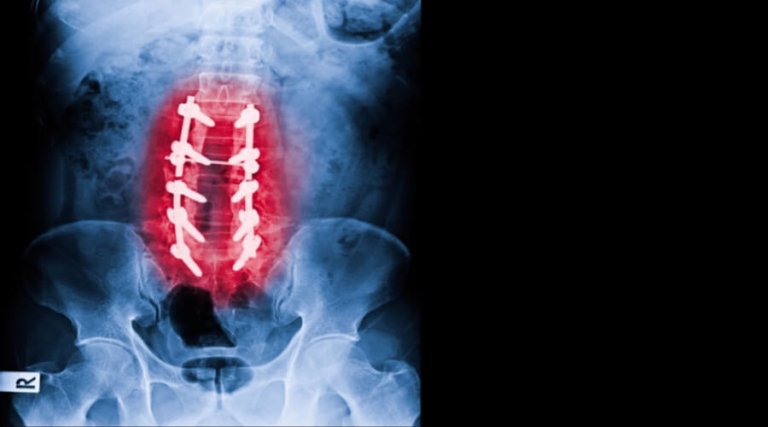

تُعد عملية تثبيت الفقرات من الجراحات الدقيقة التي تُجرى لعلاج العديد من مشكلات العمود الفقري، مثل التزحزح الفقري، والانزلاق الغضروفي المنفجر، وكسور الفقرات، وعدم إتزان العمود الفقري. وتهدف هذه الجراحة إلى إعادة تثبيت الفقرات المصابة وتقليل الضغط على الأعصاب والحبل الشوكي، مما يساهم في تخفيف الألم واستعادة القدرة على الحركة بصورة أفضل.

ورغم أن نجاح العملية الجراحية يمثل خطوة أساسية في رحلة العلاج، فإن مرحلة التعافي بعد الجراحة لا تقل أهمية عن الإجراء نفسه. إذ يعتمد نجاح النتائج على التزام المريض بإرشادات ما بعد العملية، ويأتي في مقدمتها الجلوس الصحيح بعد عملية تثبيت الفقرات، لما له من دور مباشر في حماية الفقرات المثبتة، وتقليل الضغط على موضع الجراحة، وتسريع التئام الأنسجة، والحد من المضاعفات المحتملة.